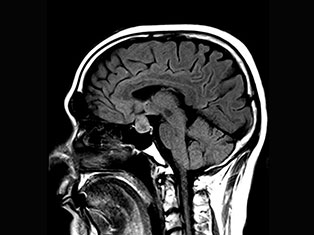

Degenerative Spine

The phrase "degenerative changes" in the spine refers to osteoarthritis of the spine. Osteoarthritis is the most common form of arthritis. Doctors may also refer to it as degenerative arthritis or degenerative joint disease.

Spinal Tumors

A spinal tumor is a growth that develops within your spinal canal or within the bones of your spine. A spinal cord tumor, also called an intradural tumor, is a spinal tumor that that begins within the spinal cord or the covering.